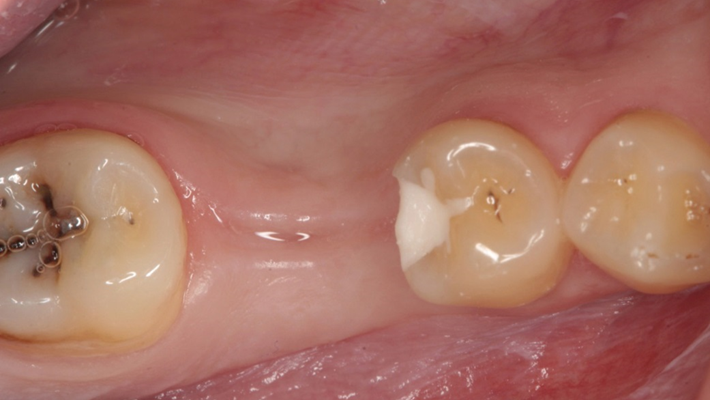

“Thin ridge expansion with minimally invasive surgery!

Use SmarThor & AnyRidge to place a wider diameter implant with minimal drilling after ridge splitting, even in thin ridge under 2mm! “

Clinical case: Ridge splitting technique using SmarThor + AnyRidge as expander

- Courtesy of Dr.Kwang-Bum Park, Korea -

AnyRidge, ridge splitting, GBR, Dr. Kwang-Bum Park, mandibular posterior, SmartThor, Mega-Oss, thin ridge, bone regeneration